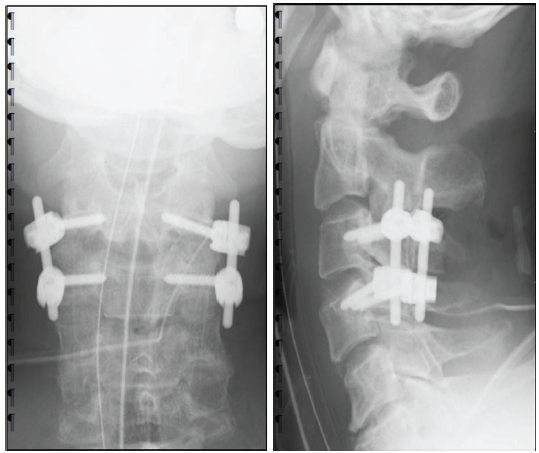

He underwent cervical posterior spinal fusion (C3/4) on the same day. Fig. 2 shows post-operative images. He was released from bed confinement with full assistance on post-operative day 2; however, he had severe ataxia and difficulty in standing with assistance. Therefore, VR rehabilitation using KAGURA, which can be performed in a sitting position with assistance, was started 1 week postoperatively. The use of KAGURA is presented in the figure (Fig. 3). Fig. 3a shows KAGURA being used by a physical therapist at our hospital, which differs not from actual patient use. The patient sat on a chair with a backrest and underwent rehabilitation. When significant trunk instability caused a risk of falling, a chair with armrests was used. One physical therapist attended, fitting a head-mounted display to the patient’s head and having them grip controllers in both hands (Fig. 3b). When gripping was difficult, the patient’s hand and controller were held with a belt, enabling them to grip the controller. There are five games built into KAGURA. In this case, two games were used: One was “a game for reaching out to targets,” and the other was “a game for catching balls falling from the sky,” both designed to be easily understood by elderly players (Fig. 3c and d). During periods of severe motor paralysis, the physical therapist assisted the patient while the game was being played. These interventions were carried out for 20–30 min/day, 2–3 times/week, depending on the patient’s condition.

Figure 2: Post-operative X-ray image of the cervical spine. C3/4 was fixed using a pedicle screw, and stability was achieved. (a) Anteroposterior view of the cervical spine. (b) lateral view of the cervical spine.